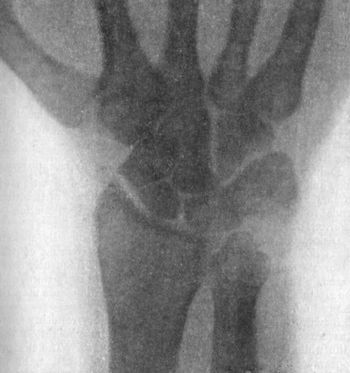

| 49. | Radiogram showing Fracture of Navicular (Scaphoid) Bone | 111 |

| 51. | Radiogram showing Forward Dislocation of Navicular Bone | 114 |